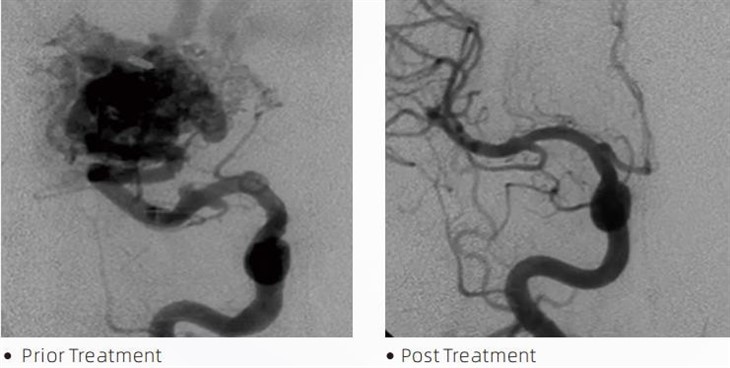

LavaTMemboliniai klijai yra medicinos prietaisas, naudojamas intervencinių neuroradiologų atliekant minimaliai invazines procedūras, skirtas gydyti tokias ligas kaip smegenų aneurizmos, arterioveniniai apsigimimai ir navikai. Lava emboliniai klijai teikia daugybę privalumų tiek medicinos specialistams, tiek pacientams dėl saugumo, naudojimo paprastumo ir veiksmingumo. Lava gali greitai ir efektyviai užsandarinti kraujagysles. Procesas apima klijų įpurškimą tiesiai į tikslinį kraujagyslę, kur jie polimerizuojasi ir sukietėja į liejinio pavidalo masę, kuri užpildo aneurizmą ar apsigimimą. Tada jis veiksmingai nutraukia kraujo tekėjimą į pažeidimą, neleidžia jam plyšti ir sumažina nuolatinės žalos ar insulto riziką. Lava apima Lava-12, Lava-18 ir Lava-34. Kiekviena formulė yra sukurta taip, kad atitiktų specifinius klinikinius poreikius. Lava-18 yra standartinė bendro naudojimo formulė. Lava-34 yra didelio klampumo klijai, skirti didelio srauto indams. Nors Lava-12 turi mažesnį klampumą ir yra labiau tekanti, todėl susidaro distalinės mikrokraujagyslės. Naudodami šias galimybes, intervenciniai neuroradiologai gali pasirinkti tinkamas Lava formules, kad užtikrintų optimalius rezultatus. Viena ryškiausių Lava savybių yra jos nelipnios savybės. Ši medžiaga yra specialiai sukurta taip, kad išliktų stabili, kol pasieks tikslinę sritį. Ši savybė reiškia, kad Lava emboliniai klijai gali būti tiksliai įterpti į arteriją ir likti ten, neprilipdami ir neprisirišdami prie aplinkinių audinių.